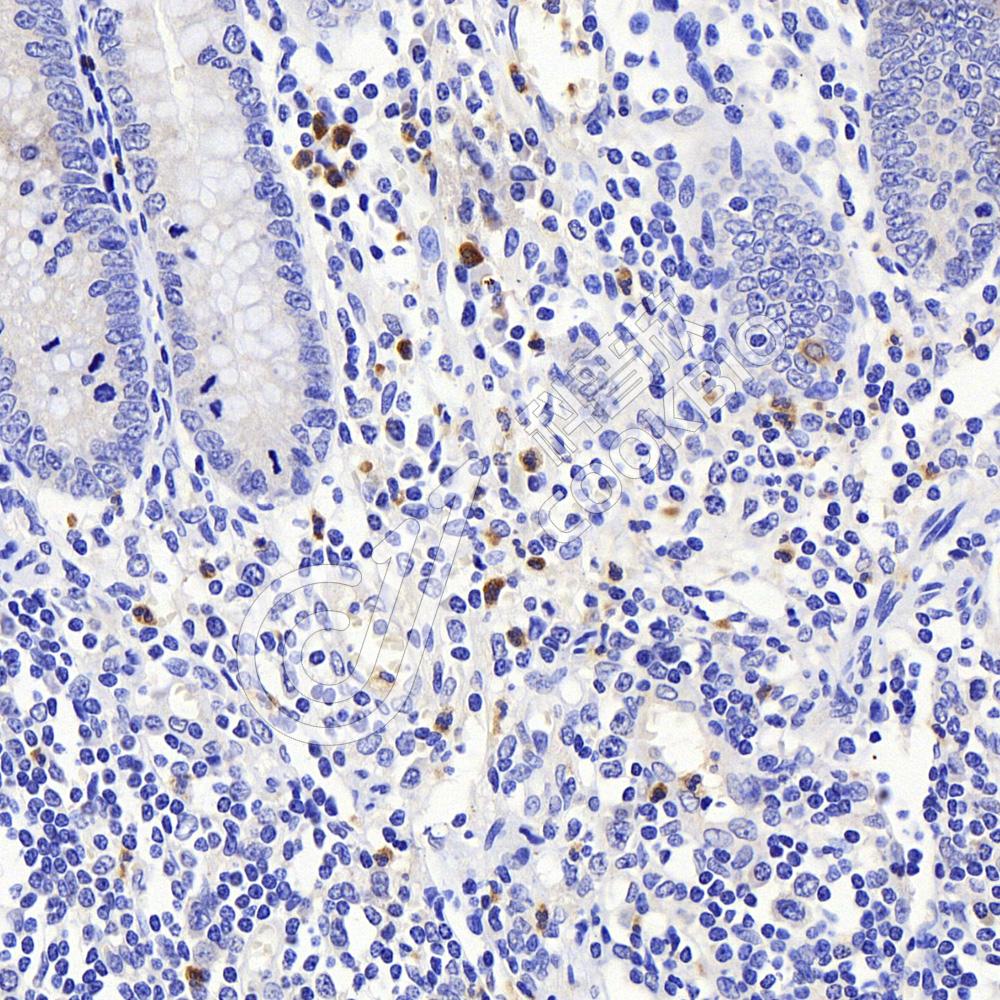

IHC检测MCP1蛋白(货号 K134830).

样品: 人阑尾, 4%多聚甲醛 (货号KSG1101) 固定12-24小时.

抗原修复: 柠檬酸抗原修复液(干粉, pH 6.0) (KSG1201), 98℃, 20分钟.

—抗: 1: 900稀释, 4℃ 孵育过夜.

二抗: S-vision免疫组化多聚二抗(山羊抗兔),即用型 (货号KB3906), 室温孵育20分钟.